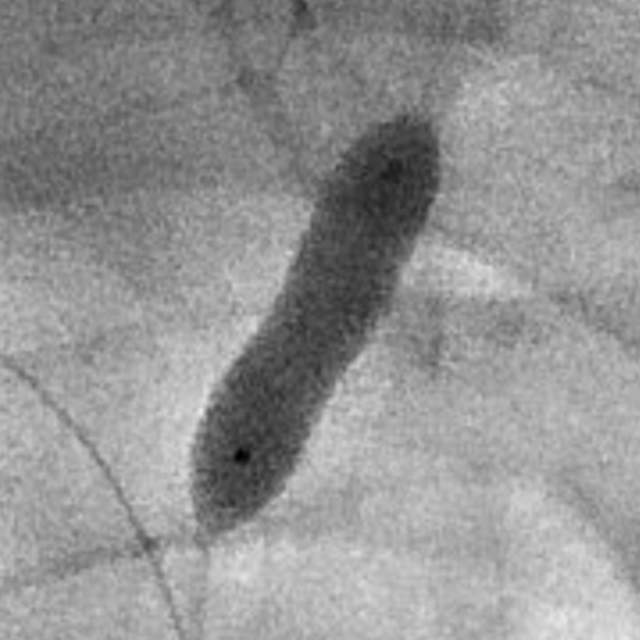

和家属商量后,我们采用全球首款椎动脉专用药物洗脱支架(Maurora)成功精准切线位植入,消除了这个“卡脖子”的狭窄……

按照说明书的介绍,与裸支架相比,Maurora可以降低再狭窄率66/……